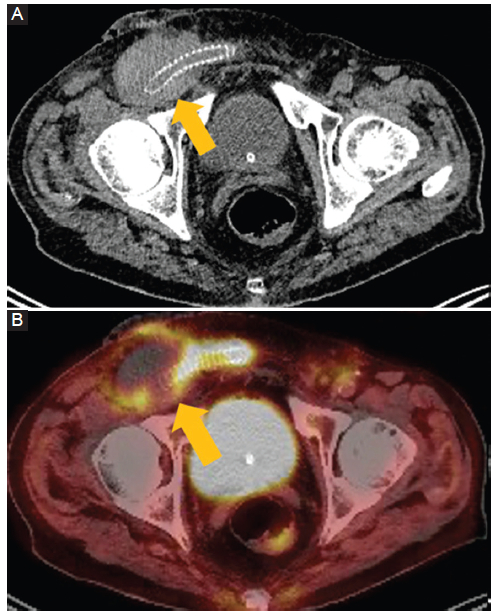

Injertos arteriales infectados

Las infecciones de injerto protésico son complicaciones poco frecuentes de los procedimientos vasculares, pero son devastadoras y con altas tasas de mortalidad2. Los injertos arteriales mas frecuentemente afectados son los aórticos, aorto-femorales, fémoro-poplíteos y carótido-subclavios (Fig. 2). Es importante destacar que puede ocurrir como hallazgo incidental en TC obtenidas por otras razones clínicas.

Figura 2

Injertos arteriales infectados. Hombre de 90 años con antecedentes de injerto aorto-bifemoral. TC con emisión de positrones de cuerpo entero con 18fluorodesoxiglucosa (FDG). A: corte axial fase porto-venosa. B: corte axial fusión. Las imágenes demuestran cambios de atenuación del tejido adyacente al injerto femoral derecho (flecha), con una mayor captación de FDG (SUV máx. 7,9).